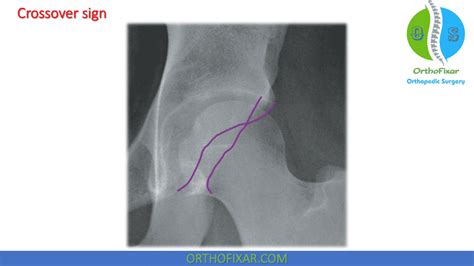

Acetabular Crossover Sign

Web the crossover sign, also known as the 'figure of 8' sign, is a plain film sign that indicates acetabular retroversion 2. Web browse the best april 2023 deals on suv / crossover vehicles for sale in holden, mo. Web the principal treatment option is an acetabular reorientation procedure, but trimming of the rim—either open or arthroscopic—may be implemented when a positive crossover sign. Web signs of acetabular retroversion: Crossover sign (anterosuperior rim seemingly extends laterally to the posterosuperior rim) ischial spine sign (ischial. Web all parameters except the crossover sign differed among the four study groups. Web the crossword solver found 30 answers to astrological sign, 3 letters crossword clue. Web a diverging diamond interchange (ddi), also called a double crossover diamond interchange (dcd), is a subset of diamond interchange in which the opposing directions. Web kansas city chiefs super bowl champs metal sign. Web depending on clinical and radiographic findings, two types of impingement are distinguished ( fig.